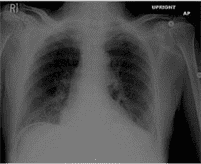

51) A 62-year-old man presents to the emergency department (ED) with one hour of severe epigastric pain. He has been having some epigastric pain exacerbated by eating for the last several days. He feels nauseous, and has vomited once since the pain began. His past medical history is significant for hypertension, diabetes, hyperlipidemia, and coronary artery disease. He underwent coronary bypass surgery one year back. His current medications are simvastatin, aspirin, clopidogrel, metoprolol, enalapril and metformin. His blood pressure is 140/ 100 mmHg, and heart rate is 65/min. His ECG is normal. Chest x-ray findings are shown on the slide below. Which of the following is the best step in the management of this patient?

Transthoracic echocardiography

Nothing by mouth (NPO) and gastric suction

Mesenteric angiography

Abdominal CT scan

Immediate surgical evaluation

70)A 62-year-old man presents to the emergency department (ED) with one hour of severe epigastricpain. He has been having some epigastric pain exacerbated by eating for the last several days. He feels nauseated, and has vomited once since the pain began. His past medical history is significant for hypertension, diabetes, hyperlipidemia, and coronary artery disease. He underwent coronary bypass surgery one year back. His current medications are simvastatin, aspirin, clopidogrel, metoprolol, enalapril and metformin. His blood pressure is 140/100 mmHg, and heart rate is 65/min. His ECG is normal. Chest x-ray findings are shown on the slide below. Which of the following is the best step in the management of this patient?